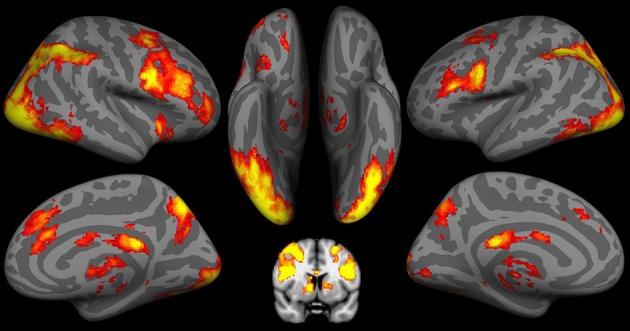

Using BOLD functional magnetic resonance imaging (fMRI) techniques, we examined the relationships between activities in the neural systems elicited by the decision stage of the Iowa Gambling Task (IGT), and food choices of either vegetables or snacks high in fat and sugar. Twenty-three healthy normal weight adolescents and young adults, ranging in age from 14 to 21, were studied. Neural systems implicated in decision-making and inhibitory control were engaged by having participants perform the IGT during fMRI scanning. The Youth/Adolescent Questionnaire, a food frequency questionnaire, was used to obtain daily food choices. Higher consumption of vegetables correlated with higher activity in prefrontal cortical regions, namely the left superior frontal gyrus (SFG), and lower activity in sub-cortical regions, namely the right insular cortex. In contrast, higher consumption of fatty and sugary snacks correlated with lower activity in the prefrontal regions, combined with higher activity in the sub-cortical, insular cortex. These results provide preliminary support for our hypotheses that unhealthy food choices in real life are reflected by neuronal changes in key neural systems involved in habits, decision-making and self-control processes. These findings have implications for the creation of decision-making based intervention strategies that promote healthier eating.

我们运用功能磁共振成像(fMRI)的BOLD技术,研究了爱荷华赌博任务(IGT)决策阶段引发的神经系统活动与蔬菜或高脂肪高糖零食的食物选择之间的关系。我们对23名年龄在14至21岁之间的健康正常体重青少年和青年进行了研究。在fMRI扫描期间,让参与者执行IGT,从而使涉及决策和抑制控制的神经系统被激活。使用青少年食物频率问卷来获取日常食物选择。蔬菜摄入量较高与前额叶皮质区域(即左侧额上回,SFG)的较高活动以及皮质下区域(即右侧岛叶皮质)的较低活动相关。相反,高脂肪和高糖零食的较高摄入量与前额叶区域的较低活动以及皮质下岛叶皮质的较高活动相关。这些结果为我们的假设提供了初步支持,即现实生活中不健康的食物选择通过参与习惯、决策和自我控制过程的关键神经系统中的神经元变化得以体现。这些发现对于制定促进更健康饮食的基于决策的干预策略具有启示意义。